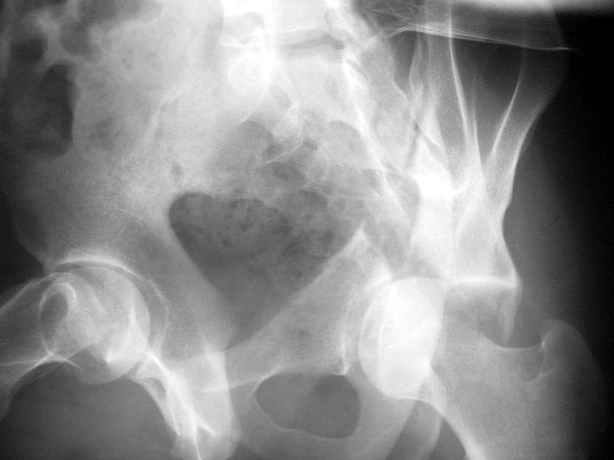

Уважаемые коллеги,Мужчина 36 лет от роду попал в ДТП 24.08.04 Рентгенограммы в приложении.

Диагноз- перелом с вовлечением таза, разрыв правого сакро-илиак сочленения vertical shear injury, перелом крыла подвздошной кости?, перелом ацетабулум Т type или Both column?, перелом шейки бедра, перелом проксимального отдела бедра.

перелом крыла правой подвздошной кости, перелом обеих колонн вертлужной впадины, двусторонний перелом лонных костей (С2.2) повреждение передних связок правого крестцово-подвздошного сочленения,

ипсилатеральный перелом шейки и диафиза бедра.

27.01.04